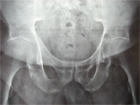

Cas clinique N°57

Dr Véra Lemaire Paris

L'intérêt de cette observation provenait de la clinique qui à elle seule permettait de localiser la lésion : il y avait un syndrome clinostatique, ce qu'une demi douzaine de lecteurs a diagnostiqué, et cette impossibilité de lever le membre inférieur du plan du lit indiquait une lésion de la région de la hanche et particulièrement du fond du cotyle. Rappelons que la mobilité de hanche était normale, ce qui excluait une pathologie articulaire.

Une scintigraphie osseuse a montré une hyperfixation, ce qui a fait discuter une maladie de Paget ; diagnostic évoqué par